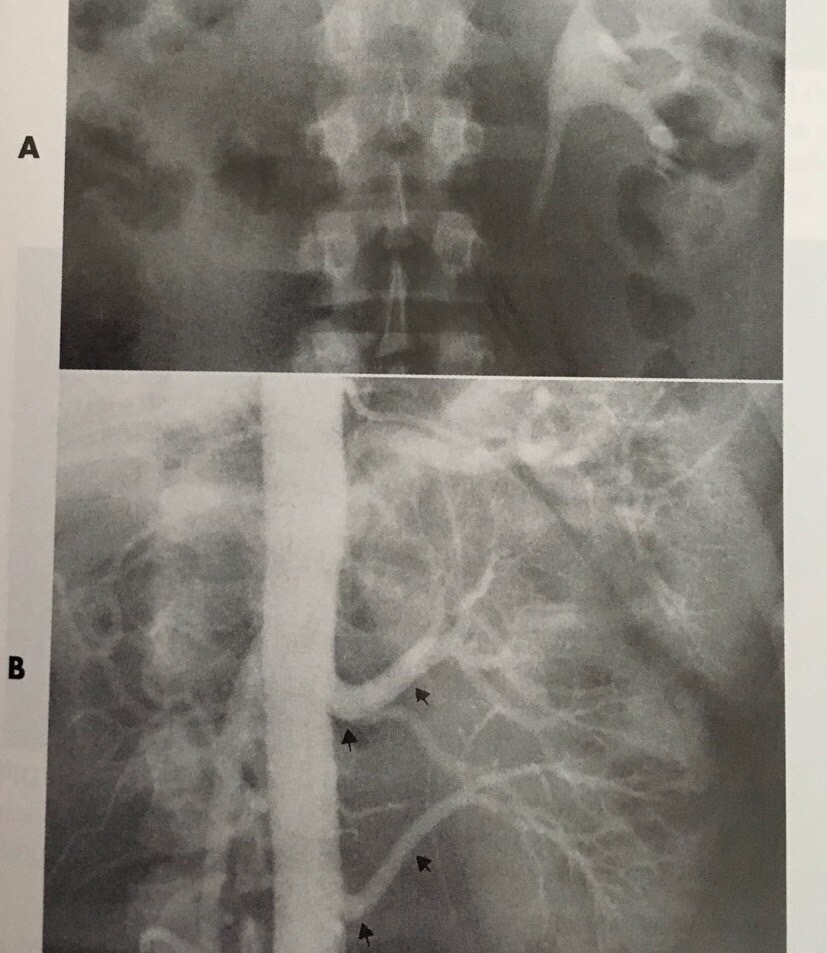

Genital Urinary Pathologies Ppt 021 Pdf Prostate Vagina Explore urinary system pathologies including utis, bph, renal calculi, and ckd. understand risk factors, symptoms, and treatment options. • discuss common congenital anomalies of the urinary system. • characterize a given condition as inflammatory or neoplastic. • identify the pathogenesis of the pathologies cited and the typical treatments for them. • describe, in general, the radiographic appearance of each of the given pathologies. Urinary tract calcifications are sometimes difficult to distinguish from other abnormal calcifications such as gallstones, vascular calcifications, and calcified costal cartilages. A comprehensive overview of radiographic pathology related to the urinary system. it covers various pathologies, including polycystic kidney, renal carcinoma, wilms' tumor, and bladder carcinoma. detailed descriptions of imaging appearances, treatment options, and key anatomical structures of the urinary system. When a patient presents with symptoms of a uti, the health care provider orders diagnostic tests that may include a urine dip, urinalysis, or urine culture & sensitivity. Diseases of the urinary system include renal and urinary tract lesions, such as inflammation, tumors, urinary obstruction, vascular diseases, metabolic diseases, and congenital malformations.